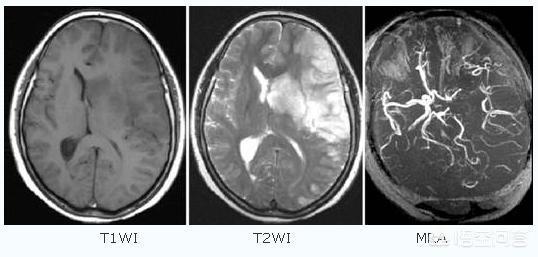

Ihr Mann brachte ihn ins Krankenhaus, wo eine Reihe von bildgebenden Untersuchungen durchgeführt wurden und die Diagnose Hirninfarkt gestellt wurde. Der Arzt empfahl, eine bildgebende Untersuchung durchzuführen und das Gerinnsel gegebenenfalls zu entfernen sowie die Symptome mit Medikamenten zu bekämpfen.

- Schlaganfälle werden unterteilt in hämorrhagische Schlaganfälle undischämischer SchlaganfallEs gibt zwei Kategorien: Die erste wird gewöhnlich als "Hirnblutung" oder "zerebrale Blutung" bezeichnet und äußert sich meist durch starke Kopfschmerzen, Erbrechen und sogar Koma und andere Symptome, während die Frage im StammDie zerebrale Infarktkrankheit bezieht sich eigentlich auf letztere。

- Zerebraler Infarkt KrankheitSie wird auch als "Hirninfarkt", "Hirnthrombose" oder "Hirnembolie" bezeichnet und äußert sich in der Regel durch eine plötzlich auftretende Schwäche oder Taubheit einer Gliedmaße, Taubheit einer Gesichtshälfte oder Verkrümmung der Mundwinkel sowie Unempfänglichkeit, Gleichgewichtsverlust, Schluckbeschwerden, Schwierigkeiten beim Sprechen, Bewusstseinsstörungen oder Krampfanfälle.

Ein Hirninfarkt, klinisch auch als ischämischer Schlaganfall bezeichnet, ist eine Störung der Blutzufuhr zu den Blutgefäßen des Gehirns, die durch eine Reihe von Ursachen wie Atherosklerose, Bluthochdruck, Diabetes mellitus und koronare Herzkrankheit verursacht wird und zu Ischämie, Hypoxie und Nekrose des lokalen Hirngewebes führt!

Schlaganfälle lassen sich in zwei Kategorien einteilen: hämorrhagische Schlaganfälle und ischämische Schlaganfälle. Der ischämische Schlaganfall (Hirninfarkt) ist die häufigste Form des Schlaganfalls in China.Ein ischämischer Schlaganfall ist ein Zustand, bei dem die Durchblutung des Gehirns aufgrund einer Obstruktion der Blutgefäße unzureichend ist, was zu einer ischämischen Nekrose und einem Funktionsverlust des Hirngewebes führt, wobei eine zerebrale Embolie und eine zerebrale Thrombose die häufigsten Ursachen sind. Vor dem ischämischen Schlaganfall können die Patienten vorübergehende Symptome einer zerebralen Ischämie (allgemein als Mini-Schlaganfall bezeichnet) aufweisen, darunter plötzlich auftretende einseitige Taubheits- und Schwächegefühle in Armen und Beinen, Sprachstörungen, verschwommenes Sehen, Gleichgewichtsstörungen usw., die nur für kurze Zeit auftreten und sich rasch wieder zurückbilden.Das ist eine wichtige Vorstufe zu einem Schlaganfall... Atherosklerotische Plaques und Stenosen der zerebralen Halsschlagadern sind wichtige Faktoren, die zu einem ischämischen Schlaganfall führen.Neben Menschen mittleren Alters und älteren Menschen gehören auch Patienten mit Bluthochdruck, hohem Cholesterinspiegel, Diabetes mellitus und Langzeitraucher zu den häufigsten Gruppen.

Der ischämische Schlaganfall ist ein Symptom einer Hirnerkrankung, die durch eine hypoxische Nekrose der blutversorgenden Bereiche der Blutgefäße verursacht wird. Ein häufiger pathogener Mechanismus:

- Zerebrale Thrombose:(1) Bildung von Blutgerinnseln aufgrund der erhöhten Blutviskosität. (2) Behinderung des Blutflusses durch die Ansammlung von Fett in den Arterien des Gehirns, das Plaque bildet und die Verengung der Blutgefäße im Gehirn verschlimmert.

- zerebrale EmbolieDie Blutgerinnsel, Fett, Luftblasen usw., die aus anderen Körperteilen als dem Gehirn stammen, gelangen über den Blutkreislauf in die Hirngefäße und verursachen eine örtlich begrenzte Unterbrechung des zerebralen Blutflusses.